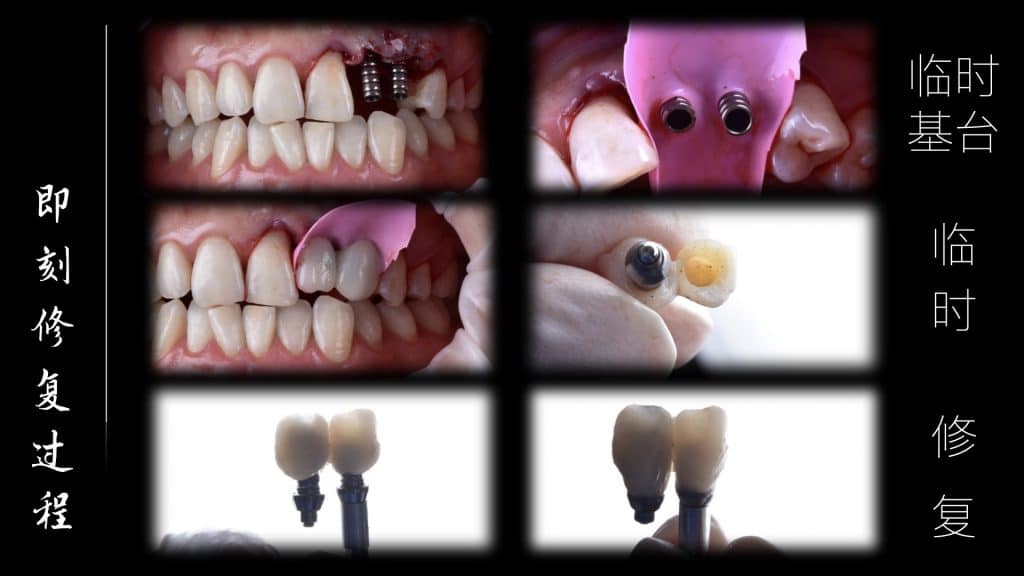

Before the start of this case, we did a fine digital design, including the design and production of temporary teeth, then CBCT matched the oral scan, designed the implant position, designed the incision method of our gums, and then implanted, and immediately repaired after completion, made a personalized gingival counter, and made a permanent restoration after 3 months.